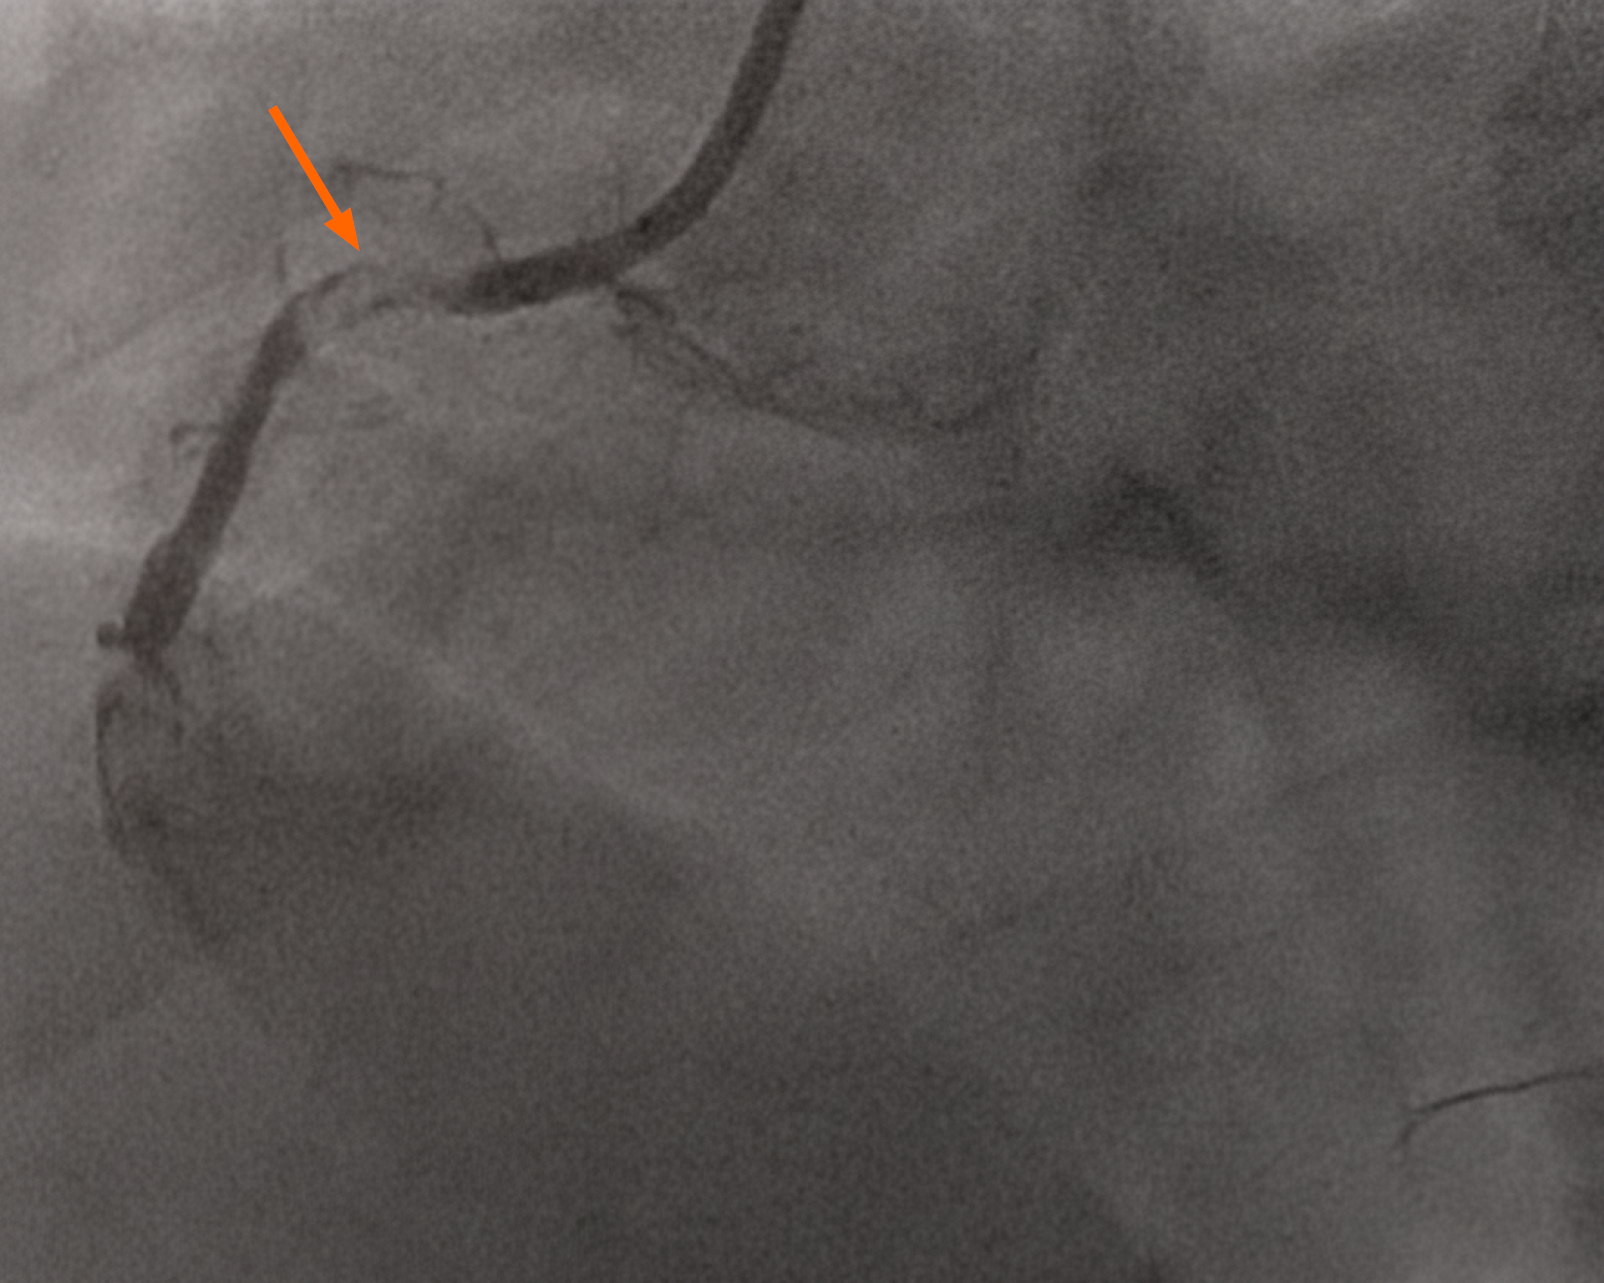

Figure 3 Coronary angiogram images after percutaneous coronary intervention done to right coronary artery showing improvement in coronary perfusion with thrombolysis in myocardial infarction grade 3 flow.